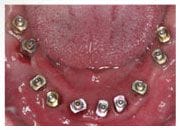

植牙過程

植入植體